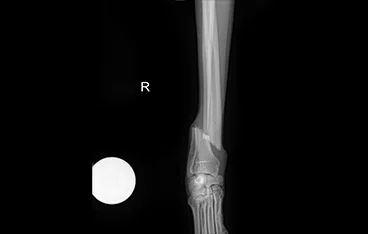

골절

골절 수복(screw, plate, k-wire, pin 등)

• PLATE

• PLATE 수술 전

PLATE 수술 후

• 복합골절

• 최소침습 골절수술